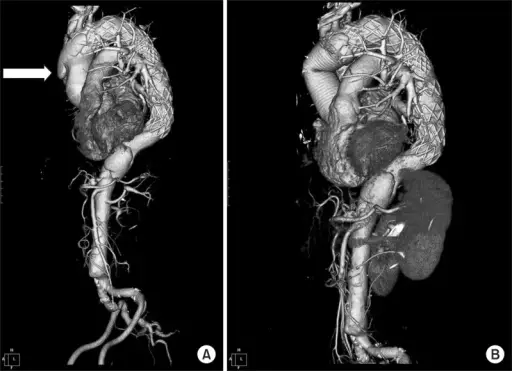

Abdominal Aortic Aneurysm

Abdominal aortic aneurysm (AAA) is an aneurysm of the abdominal aorta.

Abdominal aortic aneurysm typically develops above the aortic bifurcation but below the renal arteries.

Abdominal aortic aneurysm (AAA) is typically associated with hypertension and atherosclerosis.

Risk factors for abdominal aortic aneurysm (AAA) include:

- Male sex

- Smoking

- Elderly

- Atherosclerosis

- Hypertension

Atherosclerosis causes the vessel wall to atrophy and become weaker by raising the diffusion barrier to the media.

Abdominal aortic aneurysm (AAA) typically presents with a triad of:

- Flank pain

- Pulsating abdominal mass

- Hypotension

Symptoms of abdominal aortic aneurysm include an abdomen lump that pulses initially and enlarges over time.

Complications of abdominal aortic aneurysm (AAA) include:

- Rupture, especially when the diameter is greater than 5 cm

- Compression of nearby structures (such as the ureter)

- Thrombosis

- Embolism